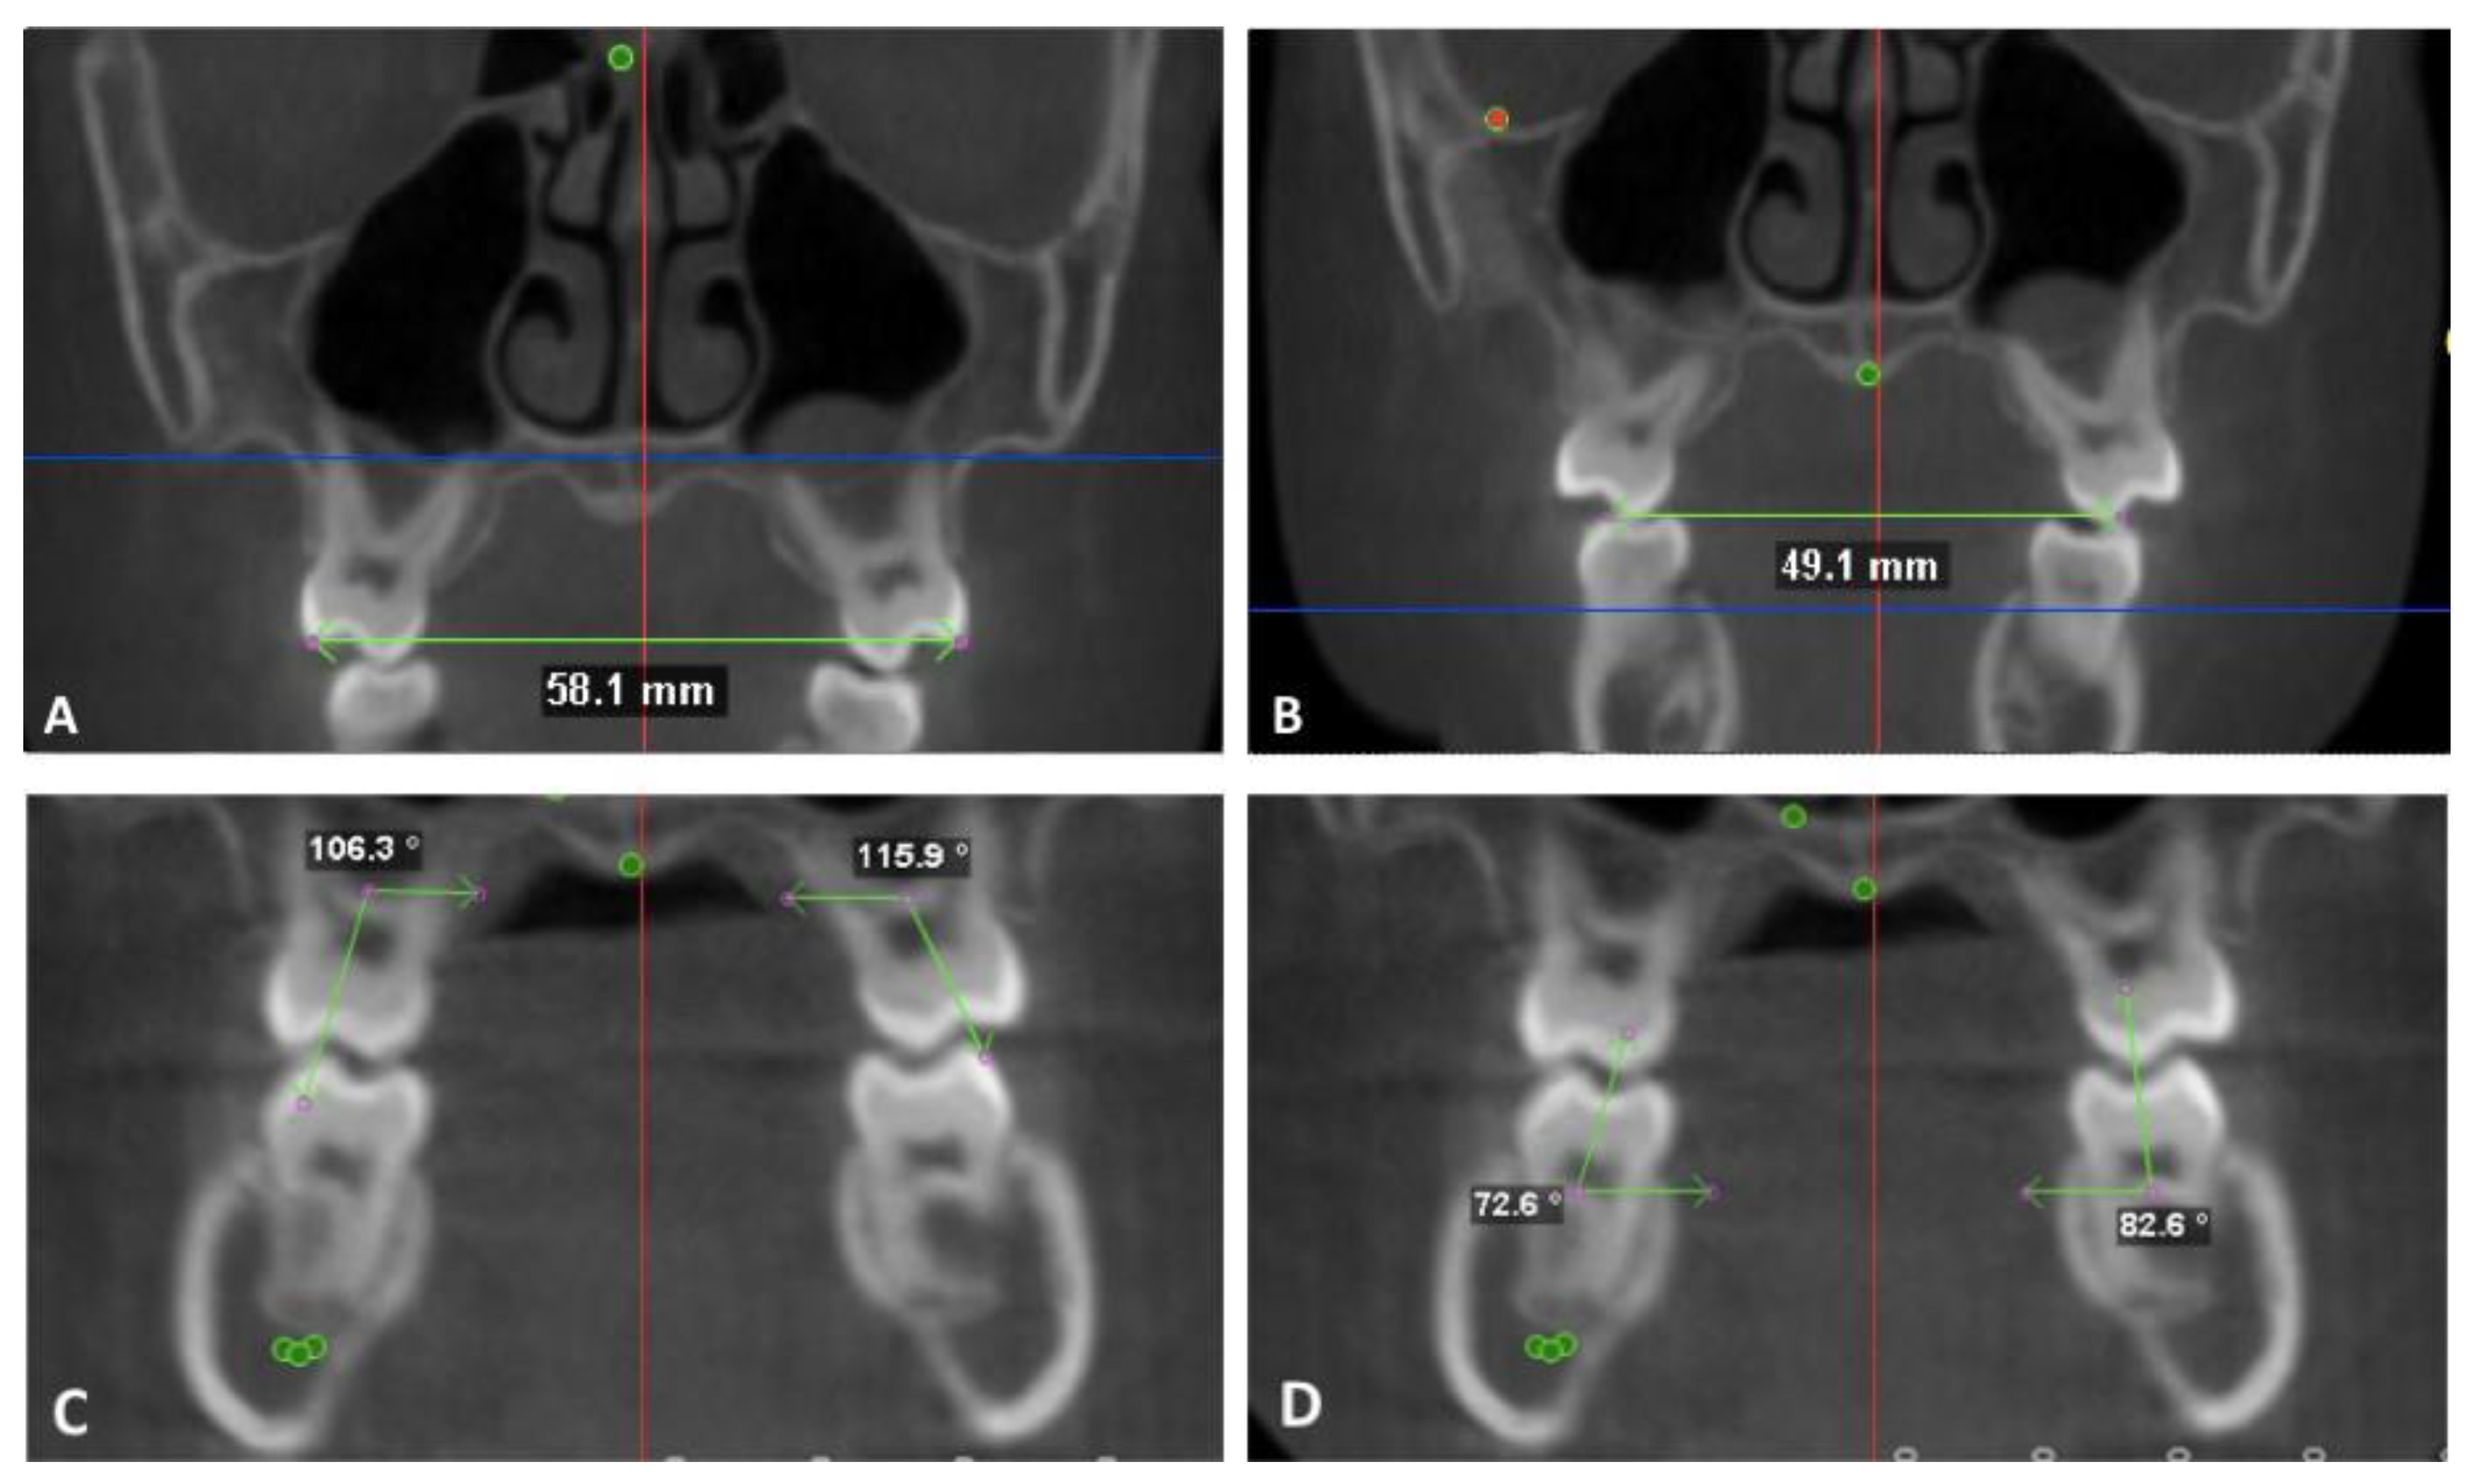

- Mx 1: 2 mm apical to the U6 CEJ on the T1 image. The most coronal axial cut on the T2 image.

- Mx 2: 6 mm apical to the U6 CEJ on the T1 image. The mid-axial cut between the most coronal and most apical cut on the T2 image

- Mx 3: 10 mm apical to the U6 CEJ on the T1 image. The most apical axial cut on the T2 image.

- Md 1: 2 mm apical to the L6 CEJ on the T1 image. The most coronal axial cut on the T2 image.

- Md 2: 6 mm apical to the L6 CEJ on the T1 image. The mid-axial cut between the most coronal and most apical cut on the T2 image

- Md 3: 10 mm apical to the L 6 CEJ on the T1 image. The most apical axial cut on the T2 image.

- Mandibular inferior border: the most inferior point on the mandibular border identified on a coronal section.